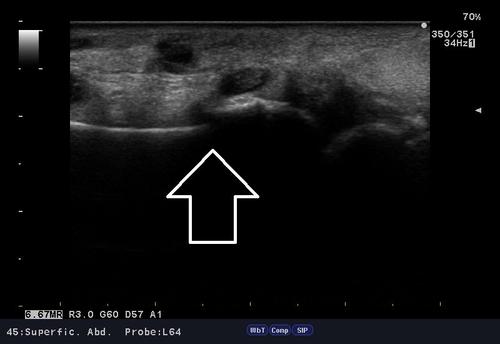

いつものように問診、視診、触診後、エコー検査。

見るからに骨折の可能性が高いです、、、

結果「橈骨遠位端部骨折」その他、尺骨頭、手根骨の骨折も疑われる為、応急処置後、提携医に診察依頼。